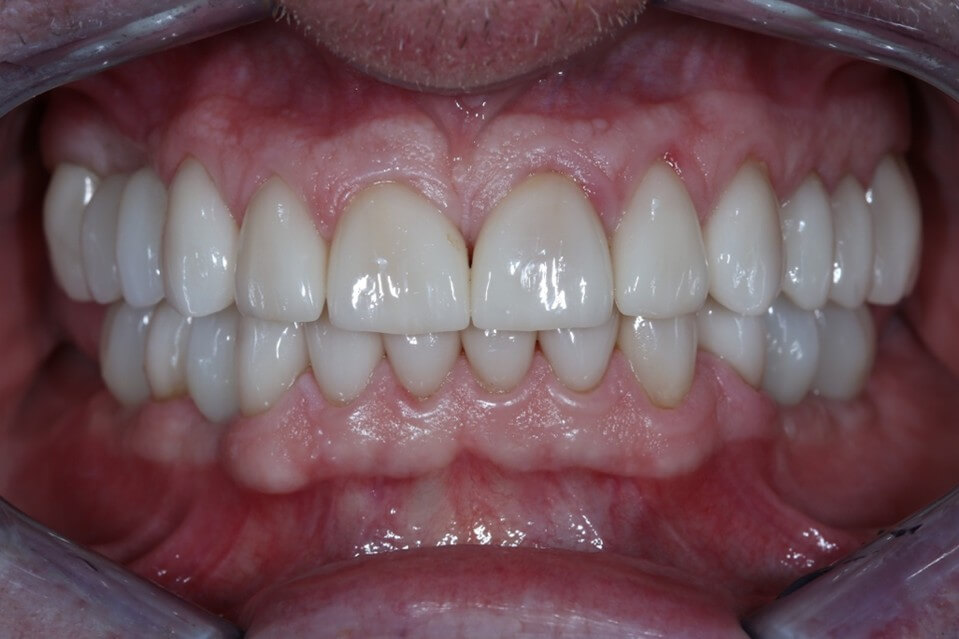

Η πλήρης αποκατάσταση στόματος (γνωστή και ως full mouth rehabilitation ή full mouth reconstruction) είναι μια οδοντιατρική διαδικασία που στοχεύει στην πλήρη αποκατάσταση της λειτουργίας, της αισθητικής και της υγείας ολόκληρου του στόματος, σε περιπτωσεις που εχουν όλα αυτά χαθεί.

Περιλαμβάνει τη συνδυασμένη θεραπεία και αποκατάσταση όλων ή σχεδόν όλων των δοντιών και συχνά των ούλων και των περιριζικών ιστών, των αρθρώσεων της γνάθου και της σύγκλεισης.

Κλινικές Περιπτώσεις